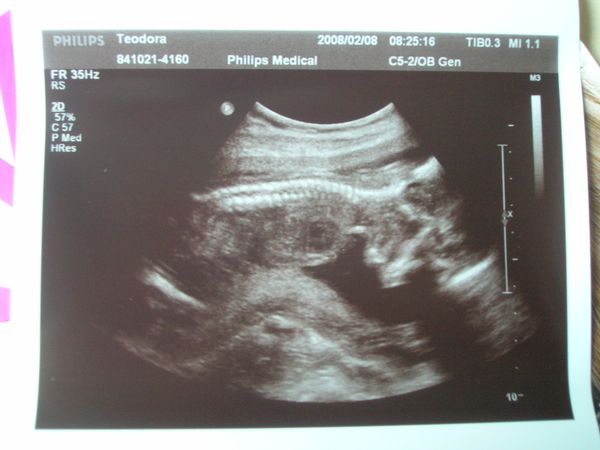

oldalnézet